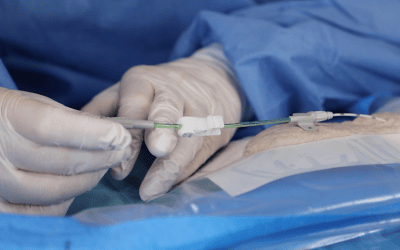

- Técnica de inserción: Seldinger directa o mediante dispositivo integrado todo en uno

- Técnica de inserción: Seldinger modificada/directa